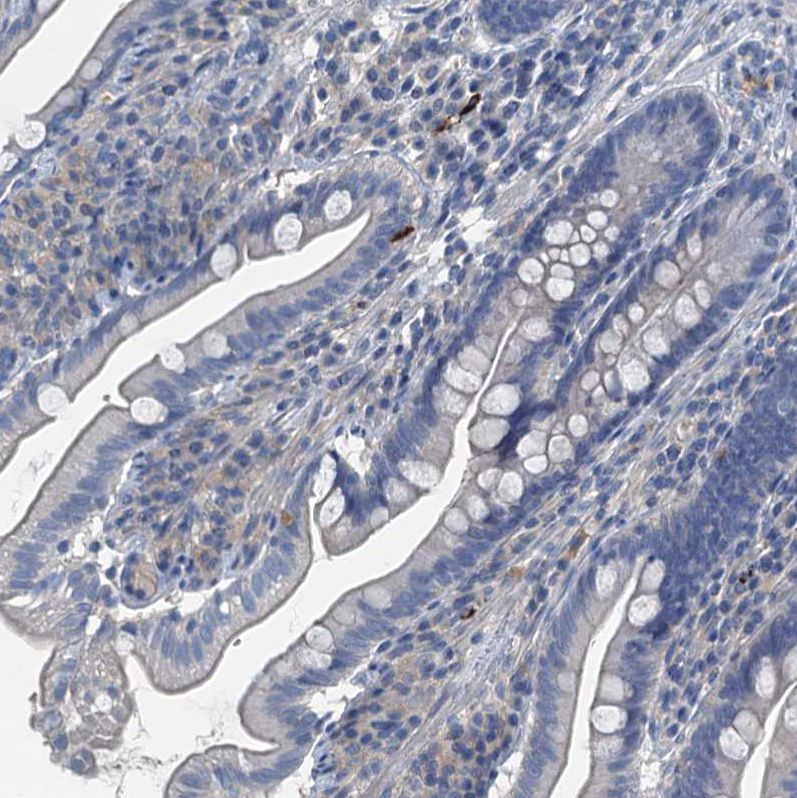

Immunohistochemistry analysis in human stomach and skeletal muscle tissues using HPA039908 antibody. Corresponding GIF RNA-seq data are presented for the same tissues.